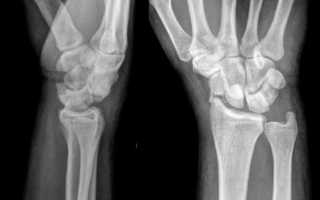

Рентгенография

Отек, болезненность, деформация в суставе или вдоль пальца должны стать поводом для рентгенологического исследования. Если на рентгенограммах не видно идентифицируемого перелома, но пациент по-прежнему испытывает значительный дискомфорт, может присутствовать скрытый перелом.

Вывих кисти руки – это распространенная травма, которая требует внимательного подхода к диагностике и лечению. Врачи отмечают, что основными симптомами являются резкая боль, отек и ограничение подвижности. При подозрении на вывих необходимо обратиться к специалисту, который проведет осмотр и назначит рентгенографию для подтверждения диагноза. Рентген помогает исключить сопутствующие повреждения костей.

Для диагностики часто назначают рентген, который помогает исключить переломы и точно определить степень вывиха. Лечение может варьироваться от консервативного — вправления сустава и иммобилизации с помощью шины, до хирургического вмешательства в сложных случаях. Важно следовать рекомендациям врача и не заниматься самолечением, чтобы избежать осложнений и обеспечить полноценное восстановление. Реабилитация включает физиотерапию и упражнения для восстановления функции кисти.